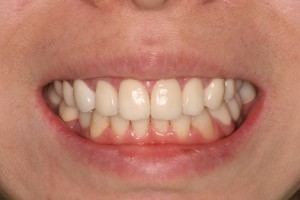

審美歯科+咬み合せ治療+インプラントの症例

治療前 ➡︎ 治療後 以前に私(帝劇DC阿部)が担当した症例をご紹介します。←左が治療...